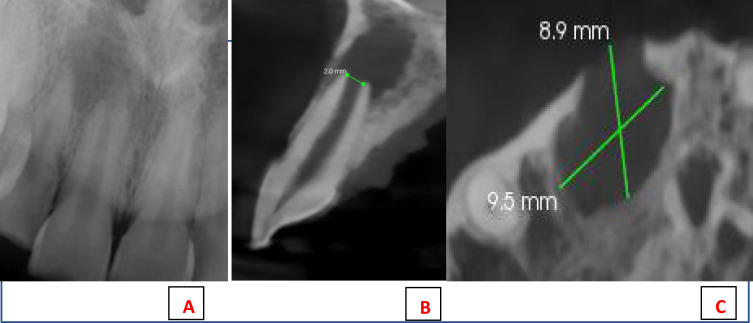

This case report details a pulp revascularization treatment administered to a mature permanent tooth exhibiting pulp necrosis. A 22-years old female patient complained of the recurrence of a sinus tract labial of the maxillary right central incisor; which was tender on biting. Diagnosis of pulp necrosis and symptomatic apical periodontitis. Preoperative periapical and CBCT radiographs showed root with wide apical foramen and large apical radiolucency. Pulp revascularization procedure was performed using 1.3% sodium hypochlorite irrigation, 17% Ethylenediaminetetraacetic acid irrigation, and calcium hydroxide intracanal dressing for 2 weeks. During the last visit, intentional bleeding was induced, collagen matrix was set over the blood clot, 2 mm of mineral trioxide aggregate and glass-ionomer filling was placed. A year of follow-up, the tooth showed no signs or symptoms and responded normally to the sensibility tests. Intra-oral periapical radiograph and the CBCT showed significant reduction in the periapical lesion's size, slight reduction in the apical foramen's size, and hard radiopaque material deposition at the root's middle third.